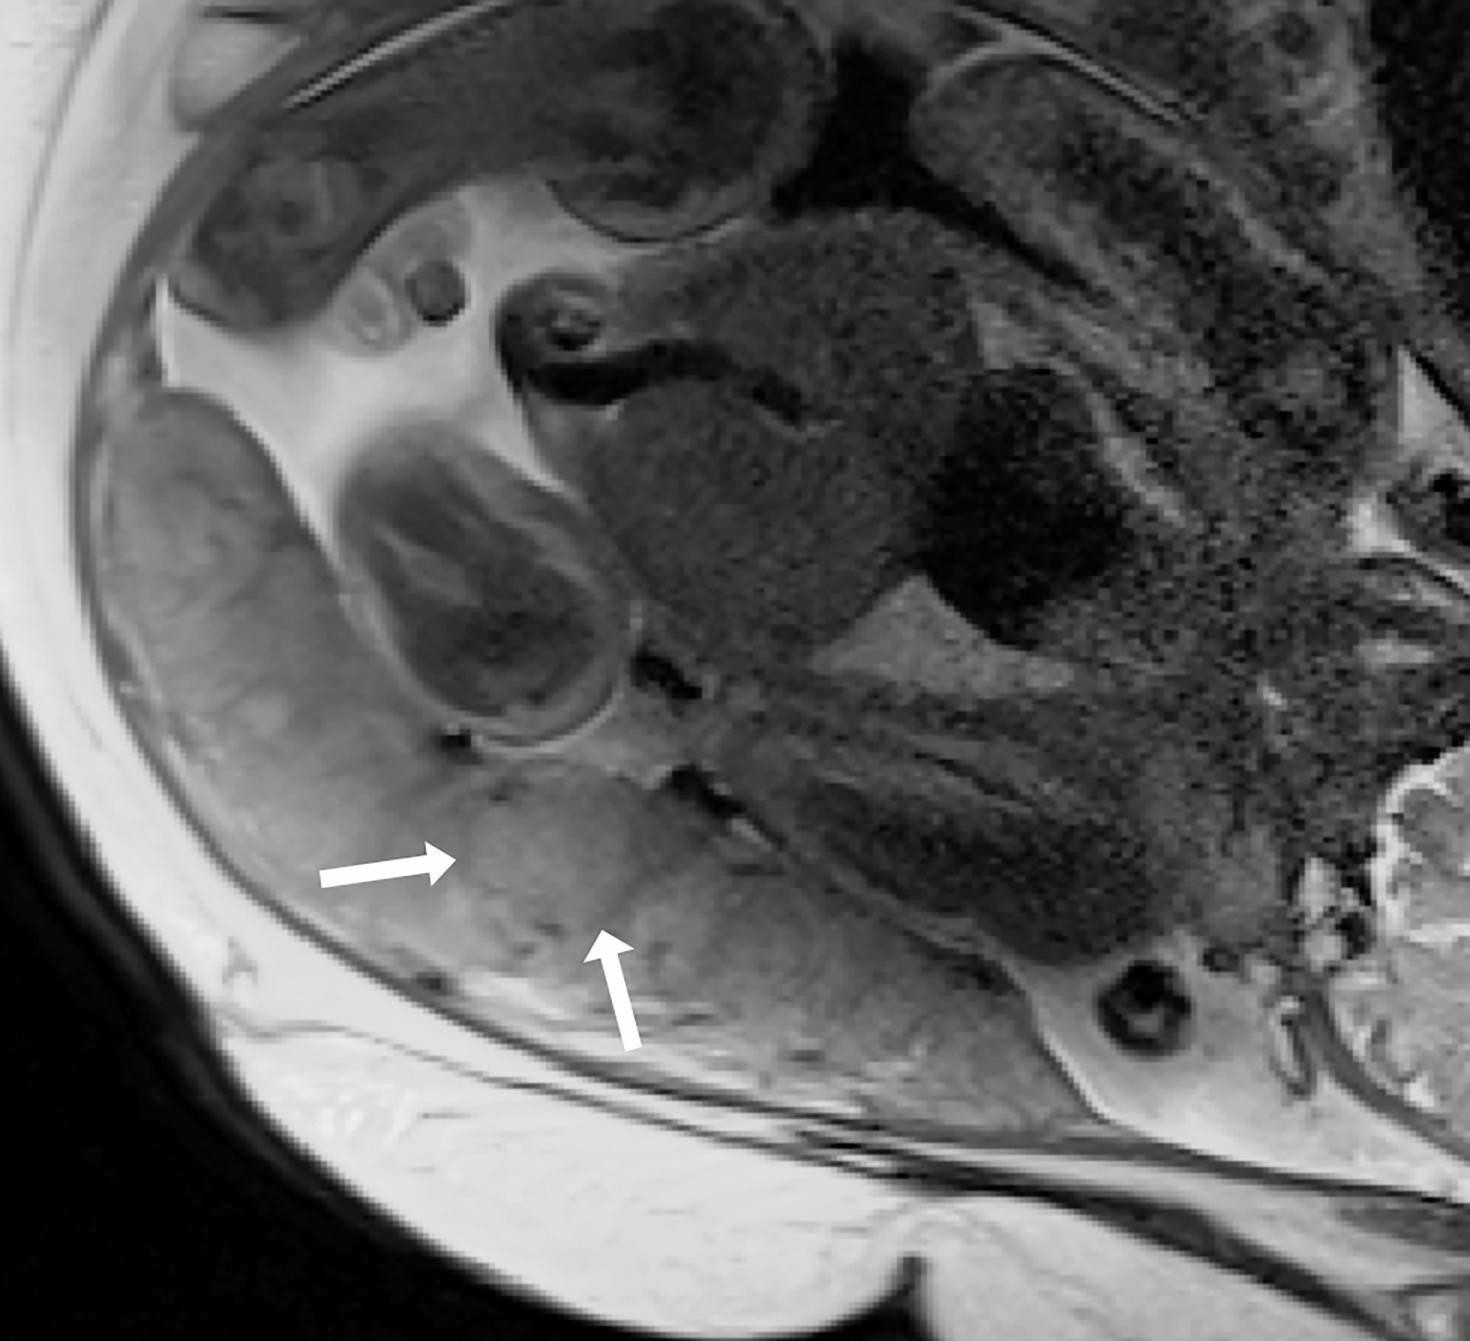

Half-Fourier Single-shot Turbo spin-Echo (HASTE) through the placenta showing the placental cotyledon surrounded by connective tissue, septa, seen as hypointense lines (arrow).